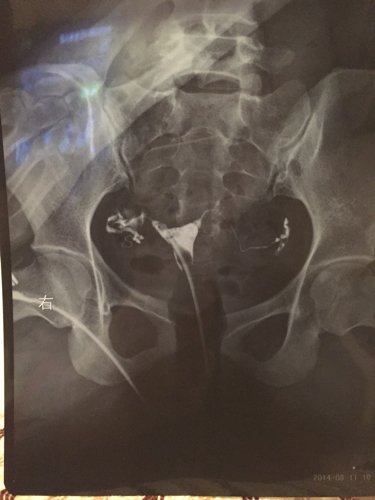

输卵管造影片子有没有问题?严重吗? 点击展开 匿名用户 2014-12-08 22:37 推荐回答 从第一张片子中可以看出右布瓣侧迂曲粘连,看图片不好禁灿行助减诊断。应该有大夫给你看过了。 斛昂杰_tguG 2014-12-09 10:24 宝宝知道提示您:回答为网友贡献,仅供参考。 相关问题 拜托各位请帮我看一下输卵管造影的片子,是个什么情况? 输卵管造影时医生让我坐起穿裤子过15分钟后再拍最后一张片子,这会影响结果的准确性吗? 输卵管碘油造影片子名字和身份证名字不对证明怎么写